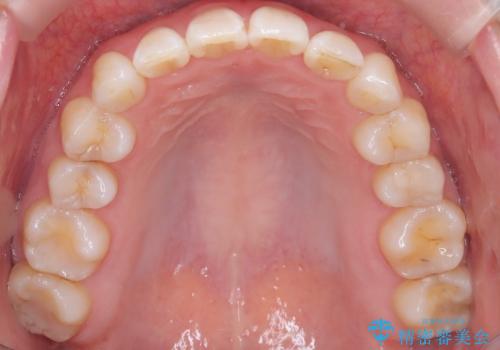

治療期間は約1年半で、ガタついていた歯列はきれいに整い、上下の前歯の真ん中もぴったりと揃えることができました。透明なマウスピースのため周囲に気づかれず治療が進み、快適に続けられたとの感想もいただいています。

現在はリテーナーで仕上がりを維持しながら、定期的に経過を見ています。